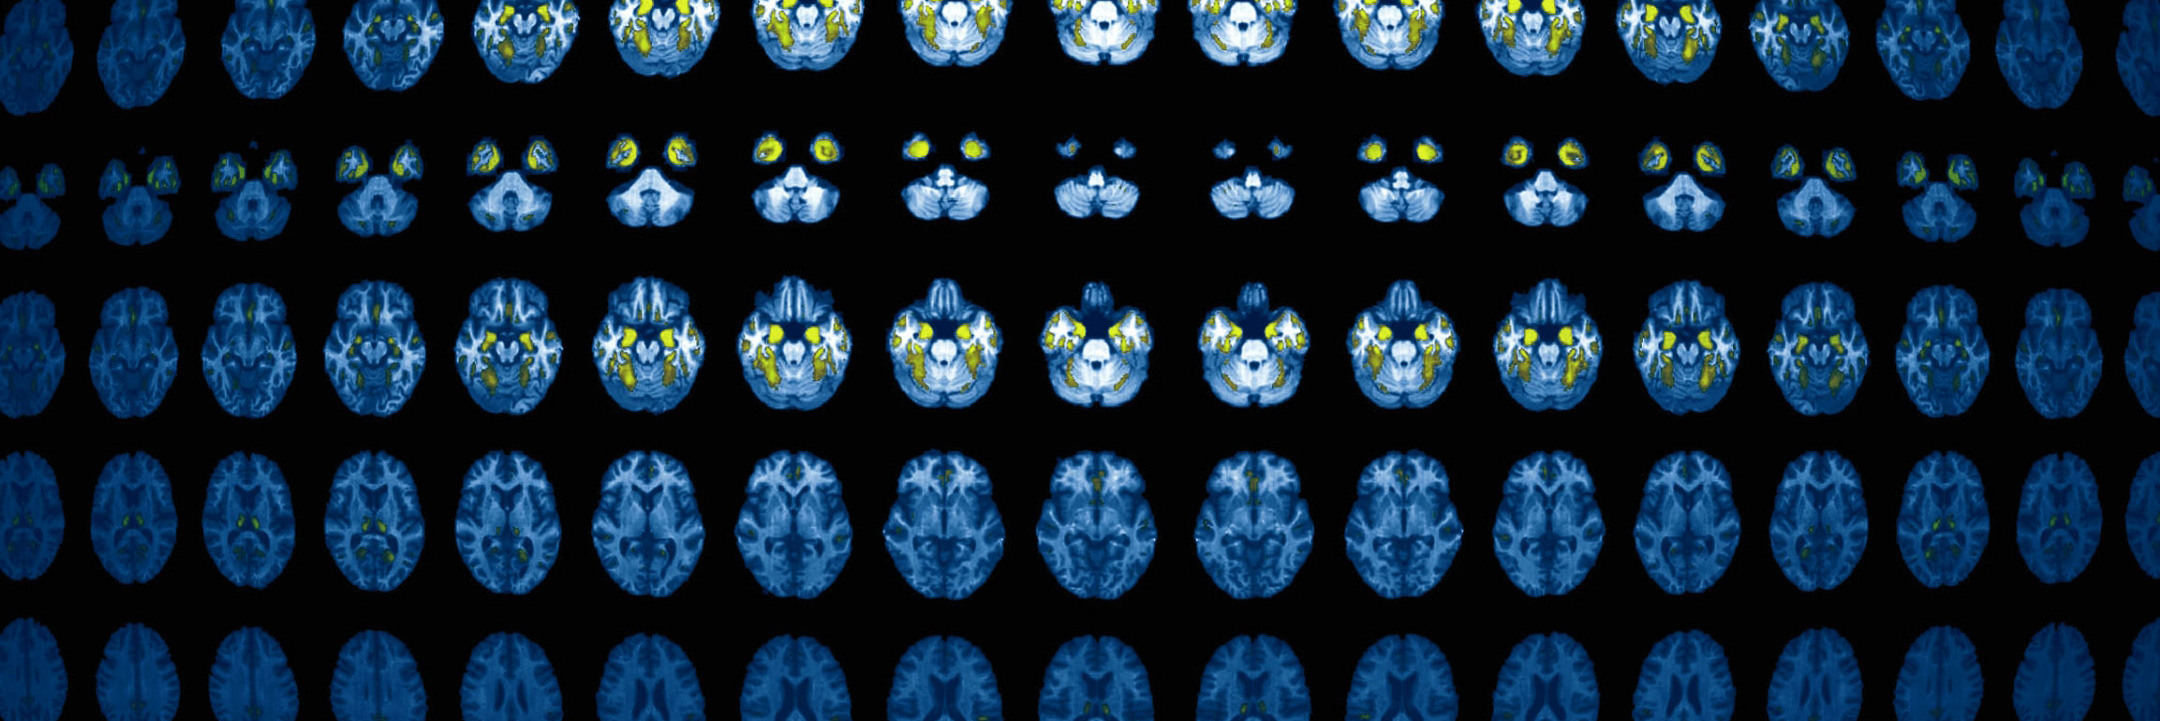

Working through data mining and machine-learning classifiers, TRACE4AD™ performs an automatic reading of the subject's brain MRI study, and it automatically identifies features of brain atrophy that begin to occur following neuronal death caused by AD along with mild cognitive impairment typical of the early stages of AD dementia.

In addition, TRACE4AD™ offers accurate volume measurements from the T1-weighted MRI study, to aid in disease categorization or tracking disease progression.